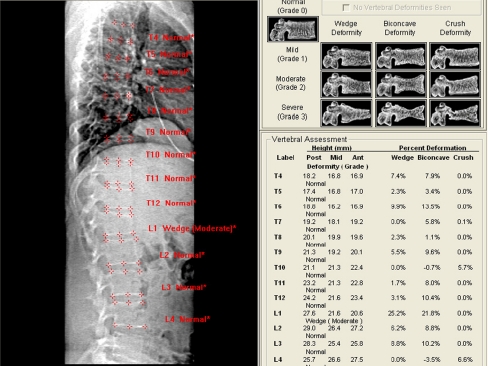

Fig. 1.

Example of a VFA study result with left the image after placing marker points, upper right the Genant classification and lower a table with the percentages of deformity. In this patient, one moderate vertebral fracture was detected: wedge shaped in L1